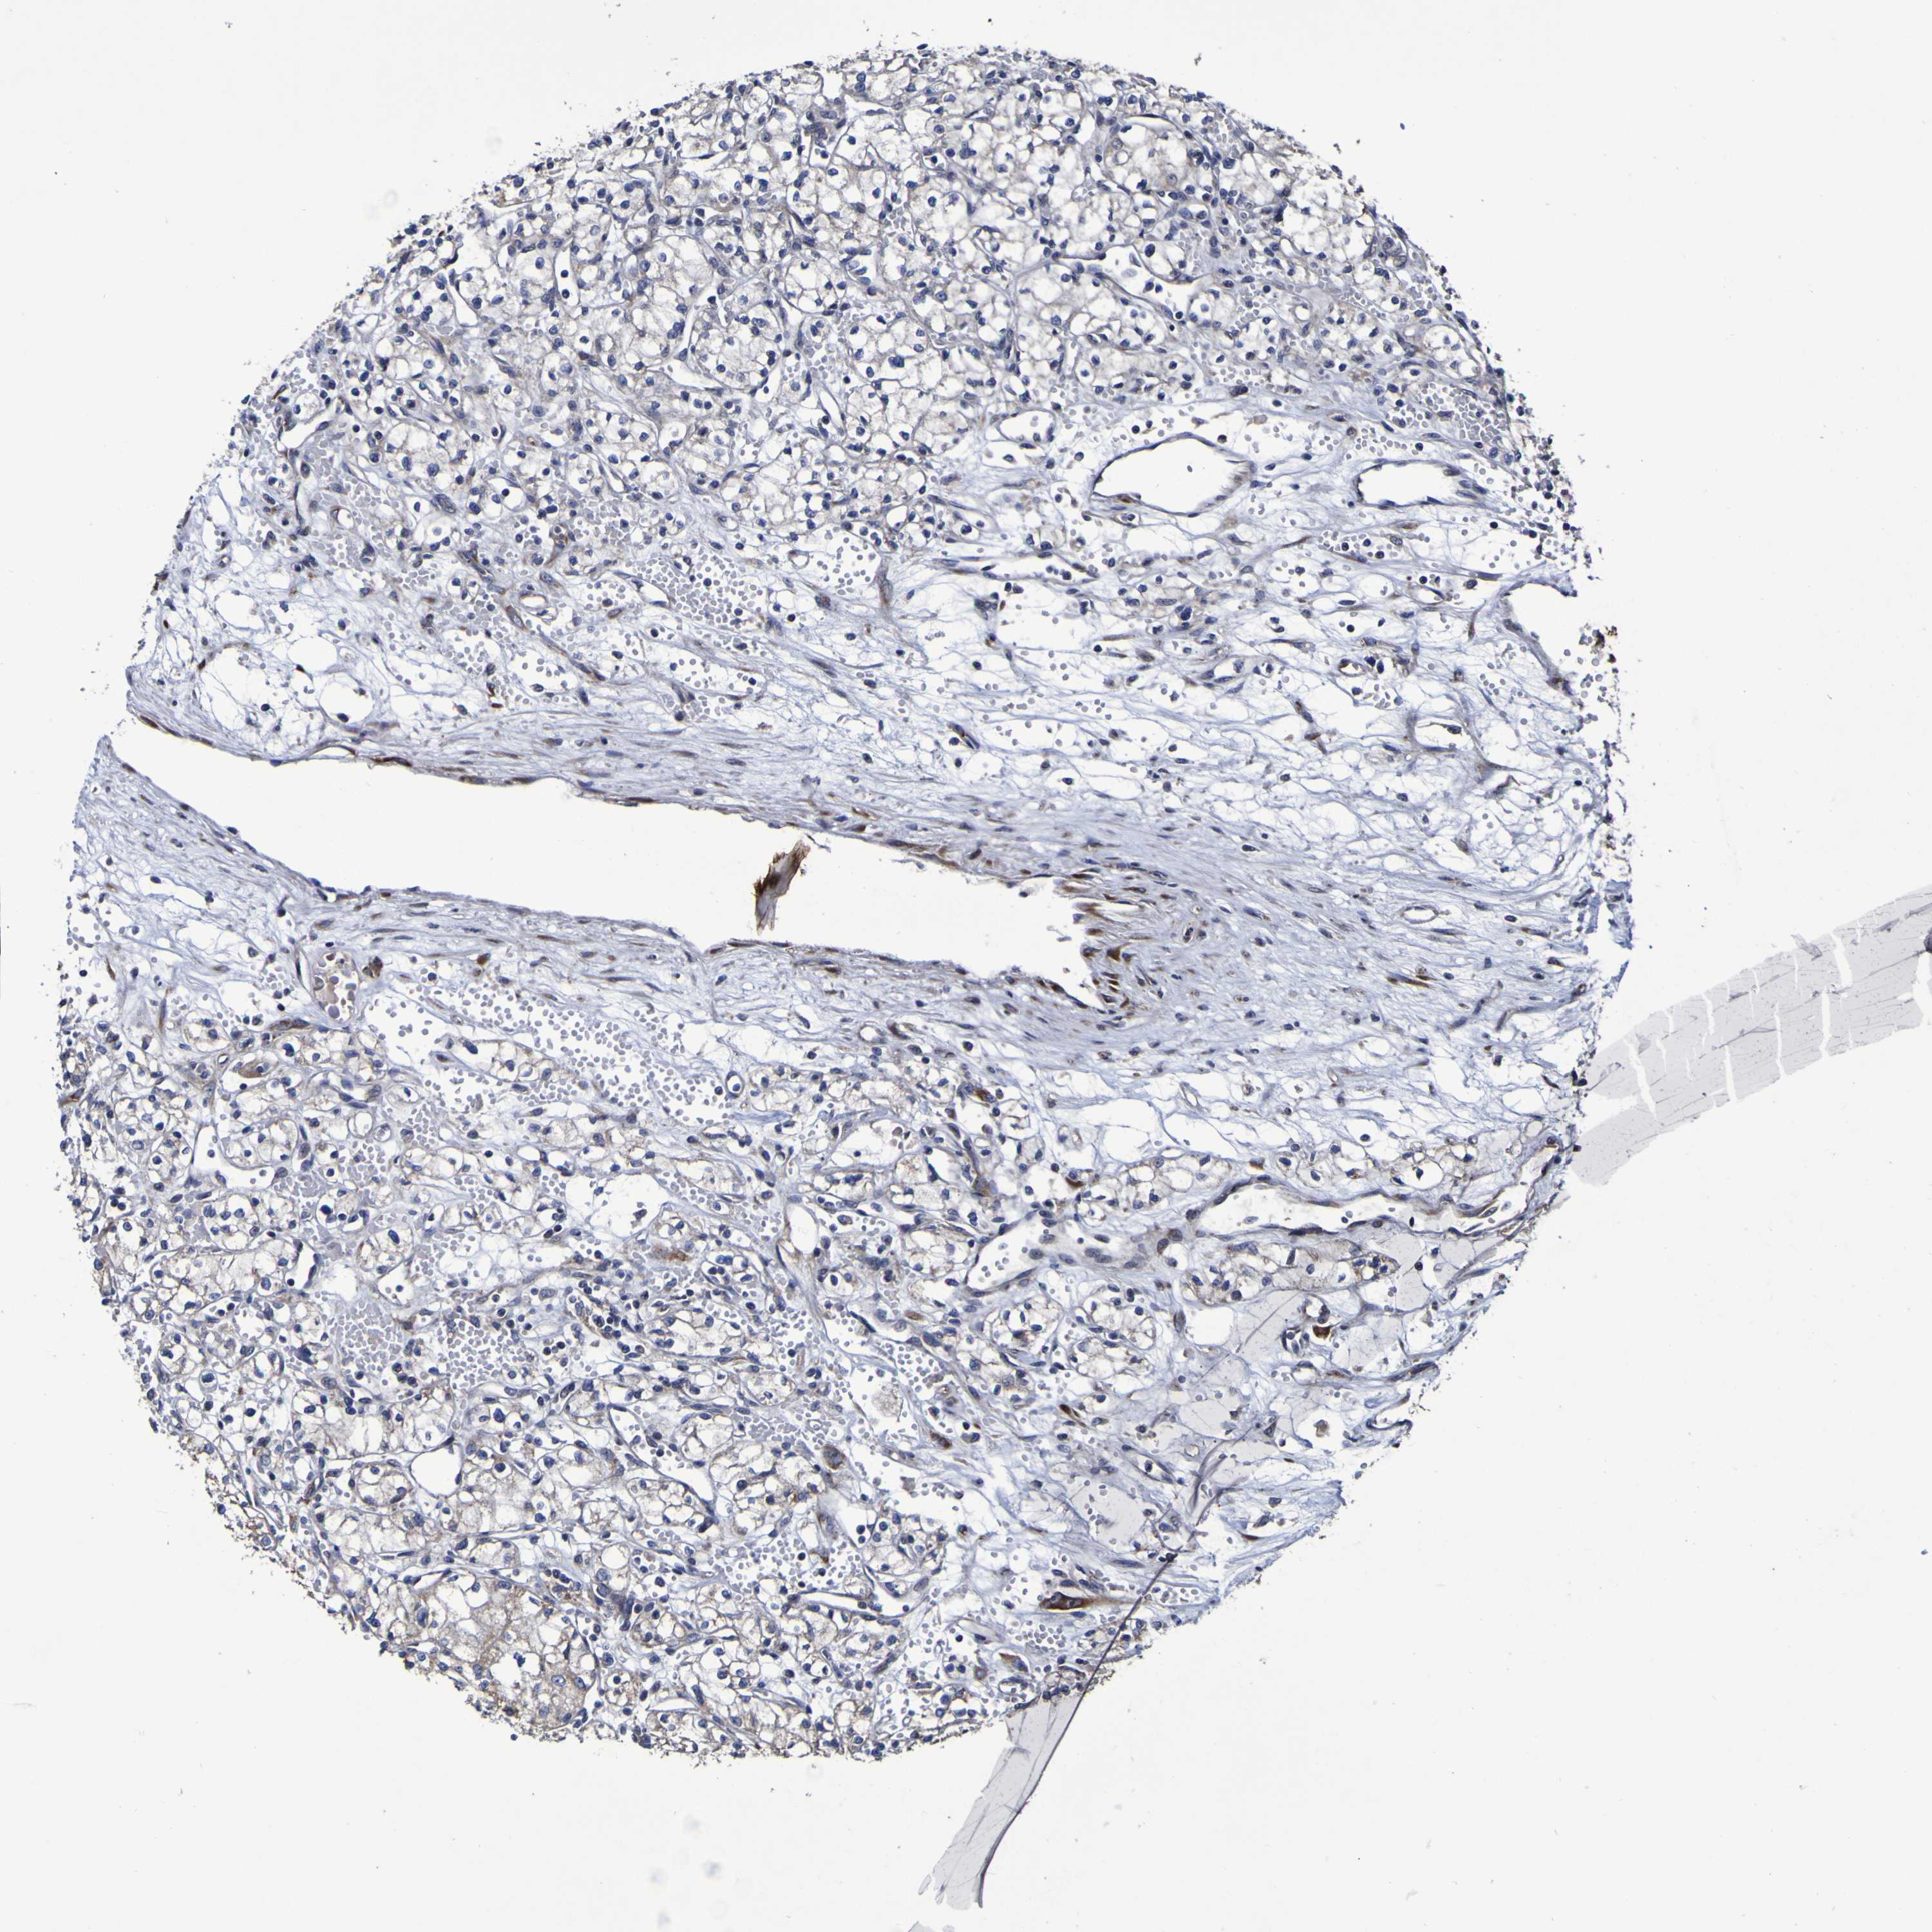

CANCER RENAL CANCER Show tissue menu

KICH TCGA KIRC TCGA KIRC VALIDATION KIRP TCGA PROTEIN RCC CPTAC PROTEIN EXPRESSION

KIDNEY RENAL CLEAR CELL CARCINOMA (VALIDATION) - Interactive survival scatter ploti

P3H1 is not prognostic in Kidney Renal Clear Cell Carcinoma (validation)

: 22.5

Average pTPM 20.6

Number of samples 100